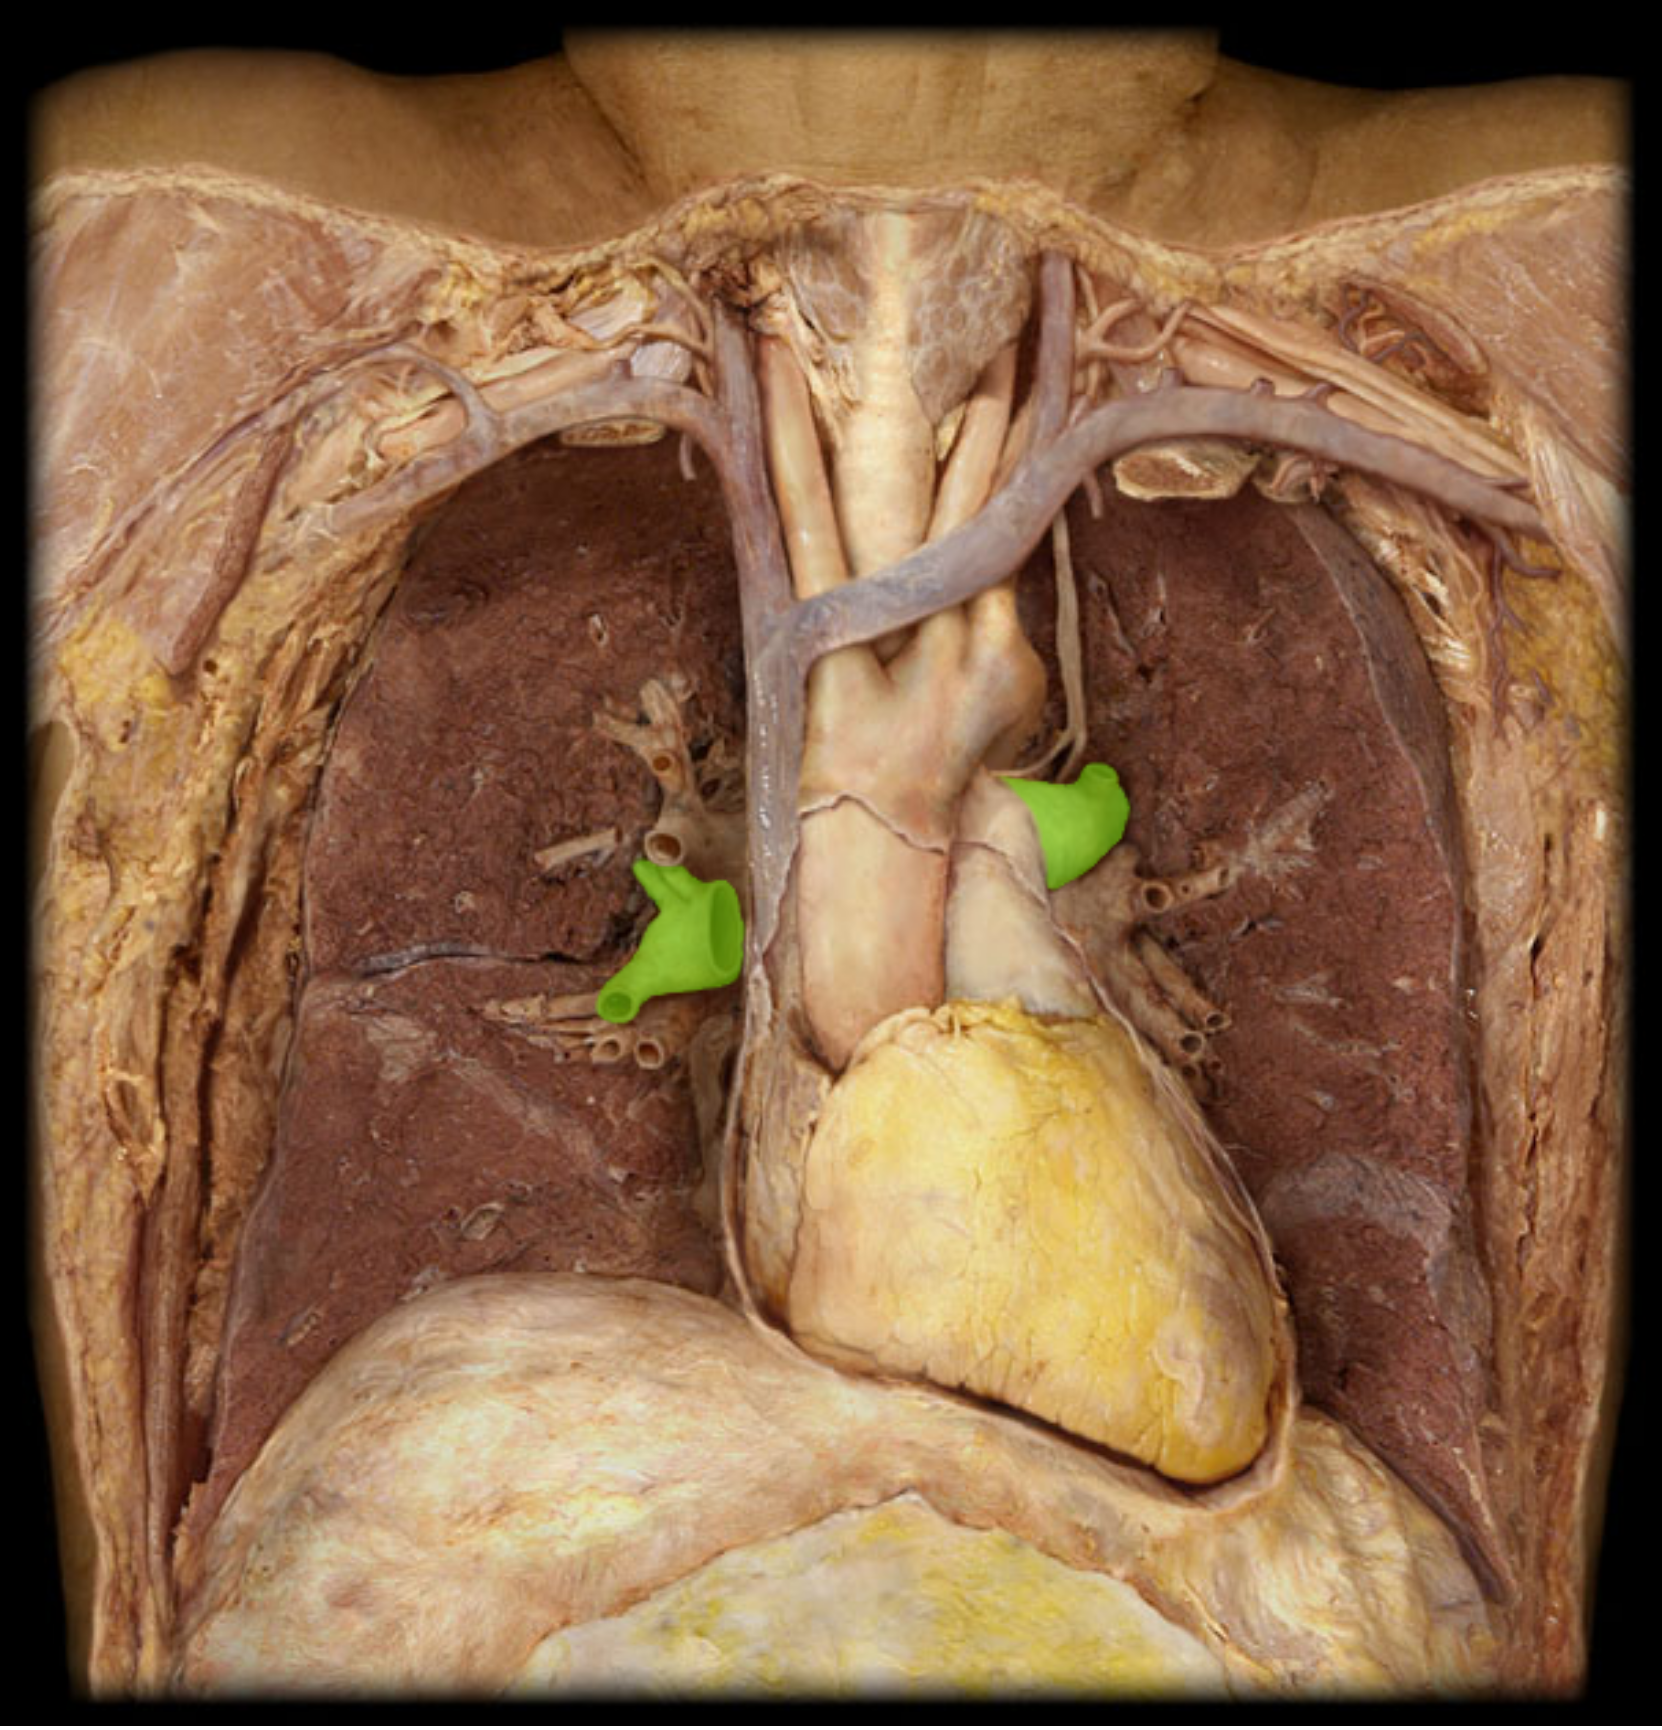

pulmonary trunk

pulmonary artery

Common carotid a.(L and R)